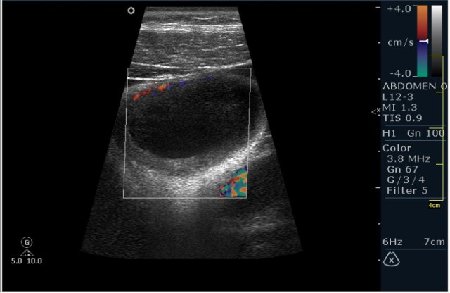

Мужчина 42 года; жалобы на периодические боли в эпигастрии. УЗИ области жёлчного пузыря выявило интересную картину; наблюдается фокальное утолщение стенок пузыря в области тела. Интересно узнать Ваше мнение?

P.S. Ультрасонография при аденомиоматозе выявляет значительное утолщение стенки желчного пузыря с мелкими эхонегативными включениями (синусами). В ряде случаев визуализируются мелкие гиперэхогенные включения, иногда с акустической тенью или эффектом реверберации – это мелкие конкременты, пузырьки газа, сгустки желчи, расположенные внутри синусов Рокитанского-Ашоффа. С помощью допплерографии определяют васкуляризацию утолщенных стенок желчного пузыря.

Мне интерено, а почему Вы решили что это аденомиоматоз? На представленных сонограммах нет признаков этого заболевания, за исключением фокального утолщения стенки (что крайне не специфично, см. ниже). Если мы не находим пристеночных синусов (Ашоф -Ракитанского) образующихся за счёт неравномерной гиперплазии эпителия ЖП с протрузией эпителия в стенку, и не видим гиперэхогенные фокусы в стенке за счёт кристаллов холестерола; мы не можем выставлять диагноз аденомиоматоз. В нашем случае мы имеем дело с равномерным гипоэхогенным утолщением (см. сонограммы призведённые линейным датчиком с высоким разрешением).